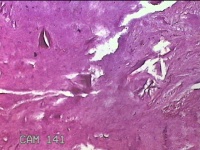

右侧中指指间关节背侧包块

性别

男

年龄

46岁

临床诊断

皮下结节

一般病史

发现右侧中指指间关节背侧一包块,伴间断性疼痛不适,考虑痛风结节。

标本名称

大体所见

灰白粉红色包块0.8x0.7x0.3cm一堆。

图4